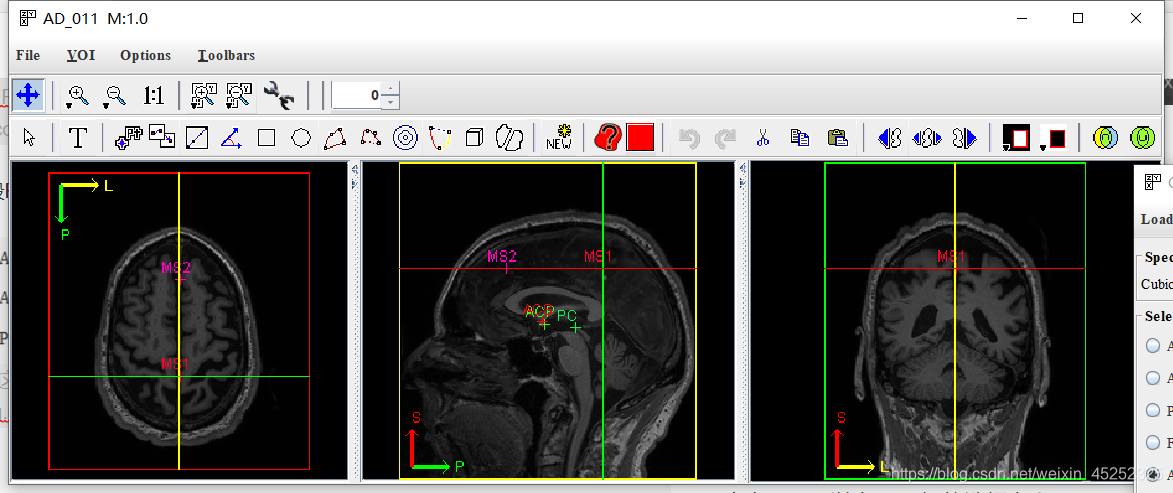

2、点击algorithm-brain tools-Talairash transformer

点击ACPC

3、正式进入ACPC处理,详细教程参考,以下也是基于该pdf来做的

目标:确定5个点的位置

(1) 设置精度,一般默认1.0

对于每个点,在三平面视图中的适当位置设置十字准线

(5) 第三个目标是标记两个中矢状点(胼胝体上方)(这一步在文中没有详细描述,所以有点模糊,参考另一篇参考)

First midsagittal point和Another midsagittal point,要求二者之间距离在20mm以上,一般就选择在和AC,PC同一矢状面上(在实践中,SG1和SG2的好候选者通常远离AC和PC,彼此之间也远离)

(6)保存变换信息:最后点击Apply,会显示ACPC结果(和原图),可以点击save保存变换信息

然后点击load,将之前的变换信息加载进去就会显示ACPC变换后的图片,点击New image to transformer栏的刷新按钮,然后选择AD_011_ACPC

然后将transformation改成acpc to orig,点击compute可以将变换后得图片和原图进行对比(不晓得有啥用)

(7)保存:在主界面上点击file-save image as,然后选择要保存的格式,进行图片保存

一般选择nii格式